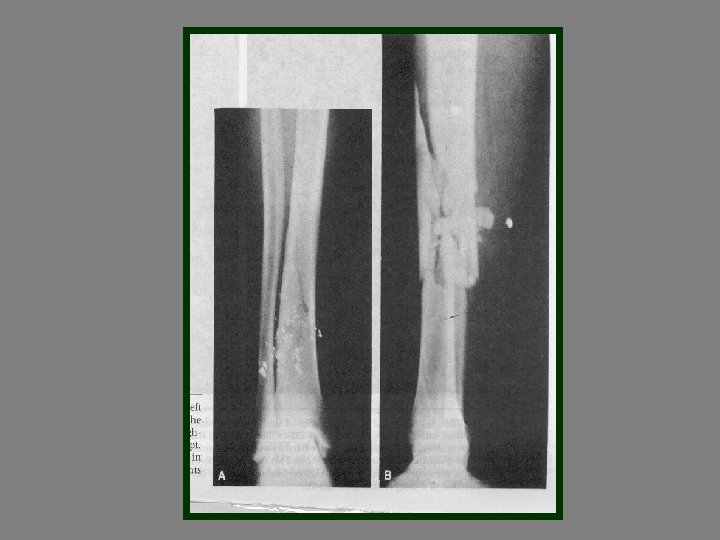

Open reduction 1 -displaced intra articular indications 2 -unstable Fr 3 -avulsion Fr 4

Open reduction 1 -displaced intra articular indications 2 -unstable Fr 3 -avulsion Fr 4 -Displaced pathologic Fr 5 - only operation indication 6 -Salter 3, 4 7 -compartment syn. 8 -NONUNION

Difinitive 1 -DEBRIDMENT 2 -FRACTURE TREATMENT A-INTERNAL FIXATION B-EXTERNAL FIXATION 3 - SKIN